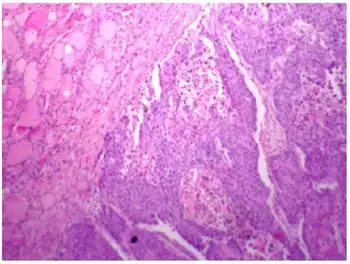

Micrograph of squamous-cell carcinoma (H&E stain)

Section from the thyroid gland shows infiltrative squamous cell carcinoma of thyroid.